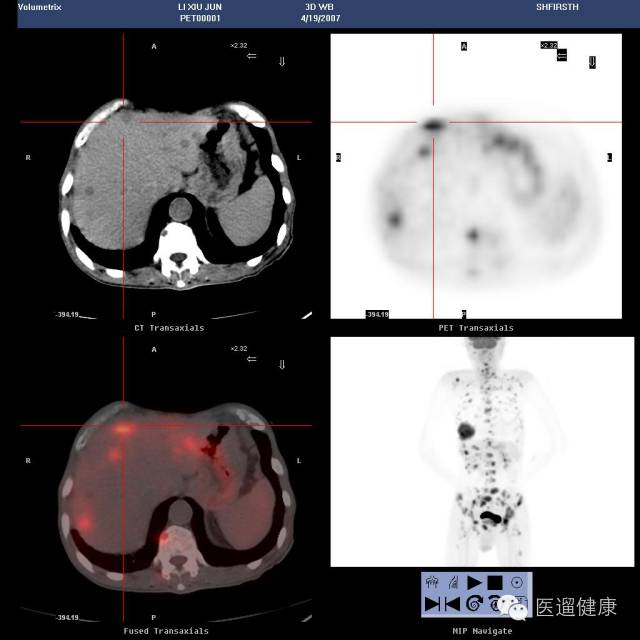

案例一、

妇科病例

病患:女,60岁。

CEA:8129.9ng/ml,CA125:3332.2U/ml

阴超:绝经后子宫小肌瘤

在这种情况下应该怎么做呢?

看看PET/CT检查后的结果。

医生随后发现该病患为左侧肺癌伴全身骨及多发淋巴结转移。